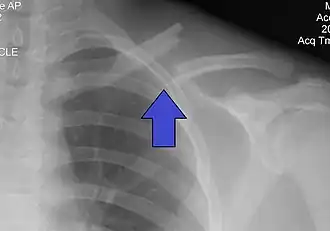

Il est radiographique affirmé par la radiographie de face. Idéalement il s'agit d'un cliché « clavicule de face » ascendant à 30° sur l'horizontale qui visualise mieux l'os et le foyer. Le fragment proximal est habituellement déplacé vers le haut en raison de la traction du muscle sterno-cléido-mastoïdien, le fragment distal étant attiré vers le bas par le poids de l'épaule et la traction du muscle deltoïde. Il se produit un raccourcissement par perte de l'arc boutant claviculaire avec un déplacement du moignon de l'épaule vers la ligne médiane.

D'un homme de 26 ans .

Sc: banque photo institut québécoise de radiologie [1]